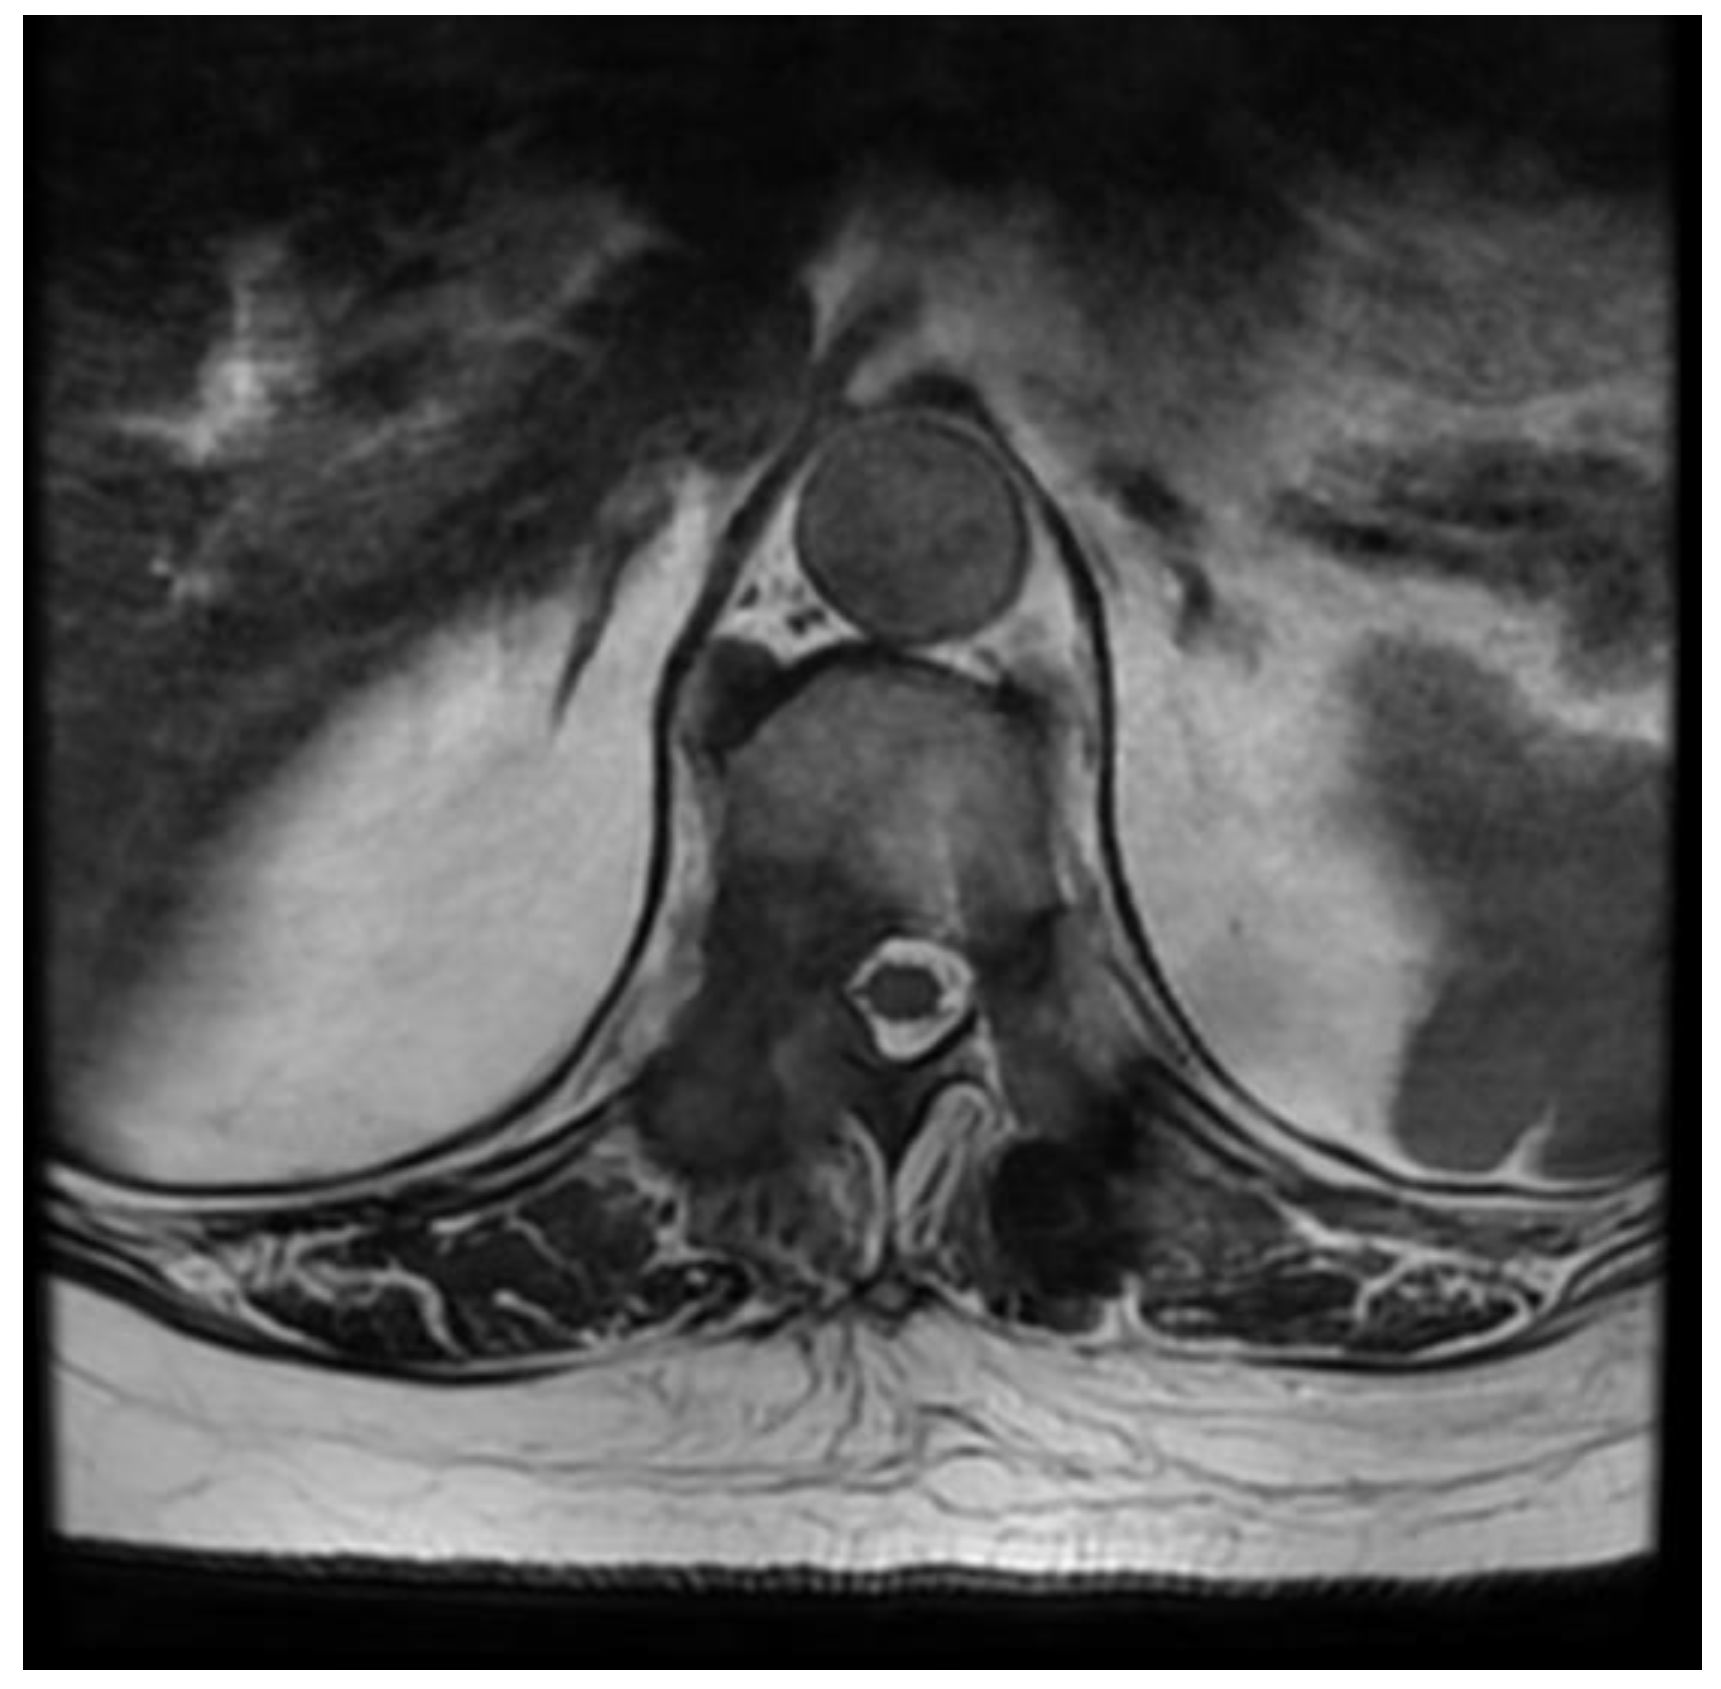

Fully Endoscopic Spine Separation Surgery in Metastatic Disease—Case Series, Technical Notes, and Preliminary Findings

- Cofano, F.; Di Perna, G.; Marengo, N.; Ajello, M.; Melcarne, A.; Zenga, F.; Garbossa, D. Transpedicular 3D endoscope-assisted thoracic corpectomy for separation surgery in spinal metastases: Feasibility of the technique and preliminary results of a promising experience. Neurosurg. Rev. 2020, 43, 351–360. [Google Scholar] [CrossRef]